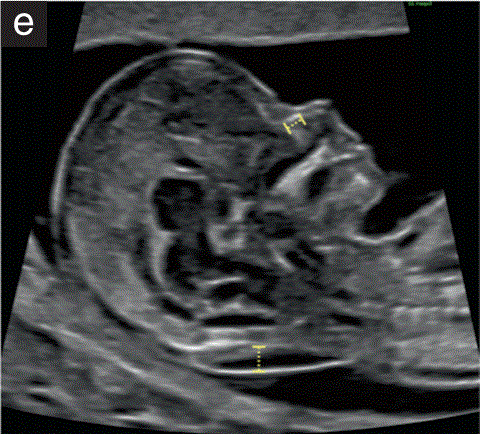

(3.4)大脑区域主要由侧脑室构成,侧脑室看起来很大,其后部三分之二几乎被轻微不对称的回声脉络丛填满(图2d)。

胎儿mt是什么检查什么疼吗【文献学习/规范指南】ISUOG实践指南(2023更新): 11-14周胎儿超声检查(全文)_https://www.jmylbn.com_新闻资讯_第9张

(d)经脑室平面的胎儿头部横断,显示正常的椭圆形头部,胎儿颅骨骨化,半球间镰将胎儿大脑分成两个相对对称的半球,脉络丛几乎填满后三分之二的侧脑室(蝶形征)。

(3.5)大脑半球看起来是对称的,由半球间裂和镰分开。大脑皮层非常薄,最能观察到到它的前部,衬着充满液体的大心室(图2e)

胎儿mt是什么检查什么疼吗【文献学习/规范指南】ISUOG实践指南(2023更新): 11-14周胎儿超声检查(全文)_https://www.jmylbn.com_新闻资讯_第10张

(e)经丘脑平面的胎儿头部横断切面,显示正常的椭圆形头部、胎儿颅骨骨化、半球间镰、丘脑、侧脑室和大脑脚。